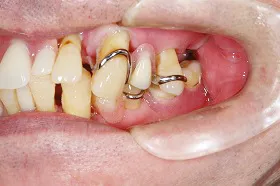

インプラントを使用した入れ歯の症例

■治療前

■治療後

| 主訴 | しっかりかみたい(咬合障害) |

| 治療方法 | 費用を抑える為、全てインプラントではなく、インプラントを土台とした入れ歯の治療 |

| 治療期間 | 約6か月 |

| 通院回数等 | 約20回 |

| 費用 | 約150万円 |

| リスク・副作用 | 術後の腫れ・痛み |